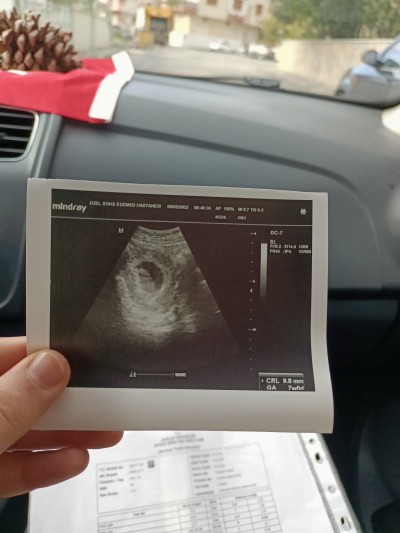

Bebeğimin kalp atışını duyduk şükürler olsun bebeğimizi de gördük  ben 6+4 sayıyordum ama doktor 7 haftalık dedi 1 ay sonra gidicez